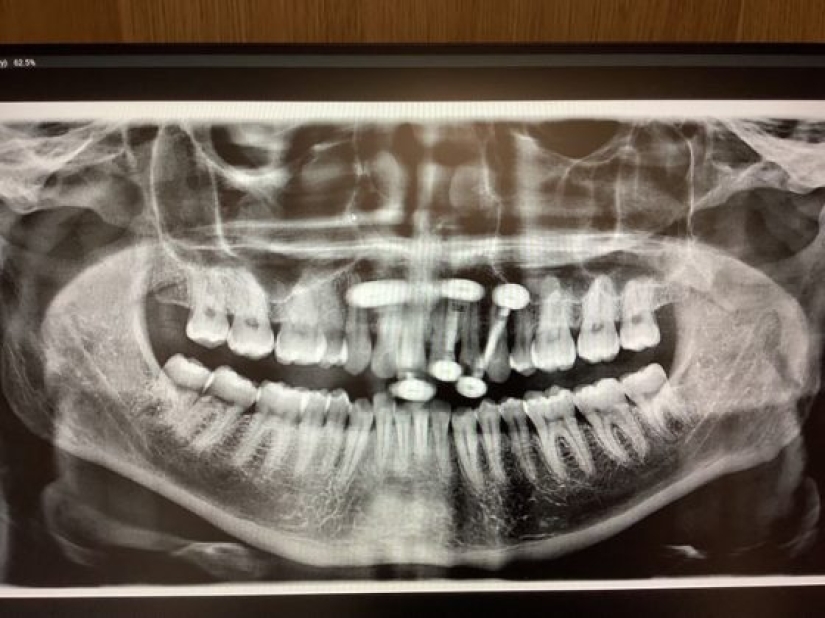

11. “En este momento, el hada de los dientes me debe mucho dinero. Tengo 33 años y aquí están mis radiografías que muestran los dientes de leche que me quedan”.